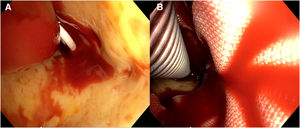

Nuestra técnica de implante de la prótesis híbrida paso a pasoTras la esternotomía, en todos los pacientes realizamos una ligadura de la vena innominada con el fin de mejorar la exposición y el acceso a los troncos supraaórticos. Colocamos un introductor de 5Fr en una de las arterias femorales y avanzamos un catéter pigtail a la aorta torácica descendente proximal con control mediante ETE. Actualmente nuestra arteria de primera elección para la canulación es el tronco braquiocefálico, mediante interposición de tubo de dacrón de 8mm. No precisa de incisiones adicionales y el acceso es rápido y sencillo. En la disección aórtica enfriamos a 28°C, y en los casos electivos, a 32°C. Durante el enfriamiento procedemos a la ligadura de la arteria subclavia izquierda en el origen y la canulamos directamente o realizamos un bypass con tubo de dacrón de 8mm, donde conectamos una línea de perfusión arterial, para así realizar perfusión de los tres troncos supraaórticos durante la parada circulatoria. La protección miocárdica la realizamos con Custodiol® (Dr. F. Köhler Chemie, Bensheim, Alemania) administrado por vía anterógrada. Si hay que actuar sobre la válvula aórtica, sobre la raíz o se requieren procedimientos asociados, se realizan durante el enfriamiento, antes de la parada circulatoria. La parada circulatoria se inicia con perfusión cerebral a través de la carótida derecha y la subclavia izquierda. Resecamos el arco generalmente hasta antes del origen de la arteria subclavia izquierda. Entonces canulamos la arteria carótida izquierda y comienza la perfusión cerebral por los tres troncos supraaórticos (fig. 7). Exploramos la aorta torácica descendente con un fibroscopio flexible, para confirmar la posición correcta del pigtail en la luz verdadera y buscar reentradas a dicho nivel (fig. 8A).

Para el implante de la prótesis híbrida intercambiamos el pigtail por una guía de soporte (Amplatz Super Stiff®, Boston Scientific, Marlborough, Estados Unidos), y sobre ella liberamos la prótesis. Realizamos la anastomosis distal en zona2 en la mayoría de los casos, con sutura continua de Prolene de 3/0 apoyada en teflón. De nuevo confirmamos la posición correcta del stent y su expansión con el fibroscopio (fig. 8B). Conectamos la rama lateral de la prótesis a la línea arterial y reiniciamos la perfusión sistémica y el calentamiento. Primero realizamos la anastomosis proximal con sutura continua de Prolene de 4-0 apoyado en teflón, finalizando la isquemia miocárdica. Finalmente realizamos la anastomosis secuencial de los troncos supraaórticos a las ramas de la prótesis con Prolene de 6/0 (fig. 9).